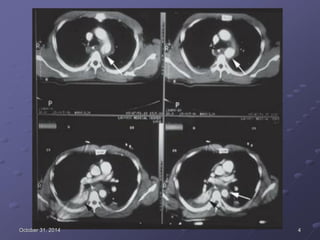

Case 4: bệnh nhân nữ, 64 tuổi, đau ngực và khó thở.

- Siêu âm: dãn thất (P) và tăng áp đm phổi.

- CT thấy tắc đm phổi nhánh phải và trái.

- Điều trị tại BVTMAG bằng thuốc tiêu sợi huyết. Đáp ứng

tốt.